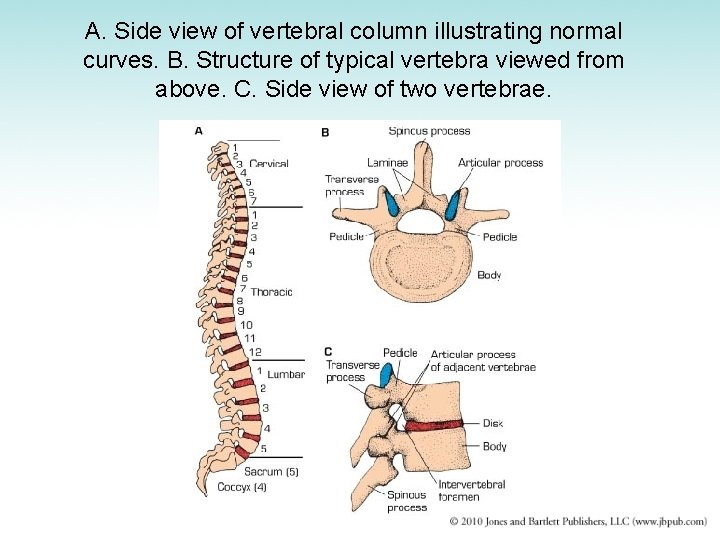

Spine • Vertebral column forms the central axis of the body – Series of vertebrae joined by intervertebral disks and fibrous ligaments – Disks: fibrocartilaginous cushions interposed between adjacent vertebral bodies; function as shock absorbers • 4 curves of vertebral column – Cervical and lumbar curves arch forward – Thoracic and sacral curves bend in opposite direction

A. Side view of vertebral column illustrating normal curves. B. Structure of typical vertebra viewed from above. C. Side view of two vertebrae.